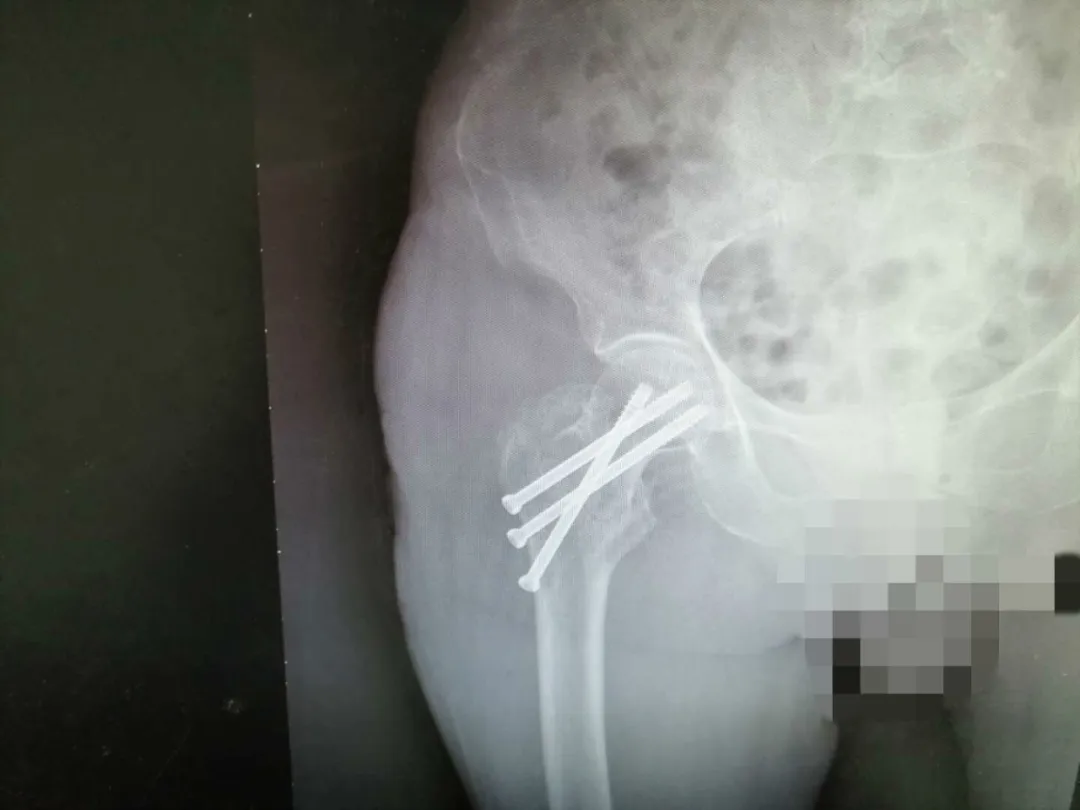

3月28日当天,手术如期进行,早上,医生查完房,护士测量了患者生命体征、评估了患者身体状况后,张奶奶在家属陪同下准时送入手术室,于此同时,我们的护理人员在做术后护理准备工作。因为是手术患者,加上要长期卧床,我们一般都会更换床单,保持整洁,保证了患者卧床期间有个良好的舒适感,也可以降低感染和褥疮发生的风险,并在其床头放置好心电监测仪和备好吸氧等测量生命体征的用品,以备不时之需。两个小时过去了,手术顺利完成,张奶奶被送回病房进行后续康复治疗,护士加强了护理措施,防压疮、防跌倒、防坠床。

在住院期间,张奶奶和家属对谢主任、梁医生表示再三感谢,对护理人员的服务态度和护理措施赞不绝口。家属为了方便照顾患者,有更好地营养支持,术后5天患者要求回家静养,护士对其耐心地交代清楚回家后的注意事项、患肢的功能锻炼。办理出院手续时,张奶奶再一次的对谢主任、梁医生表示了由衷的感谢。